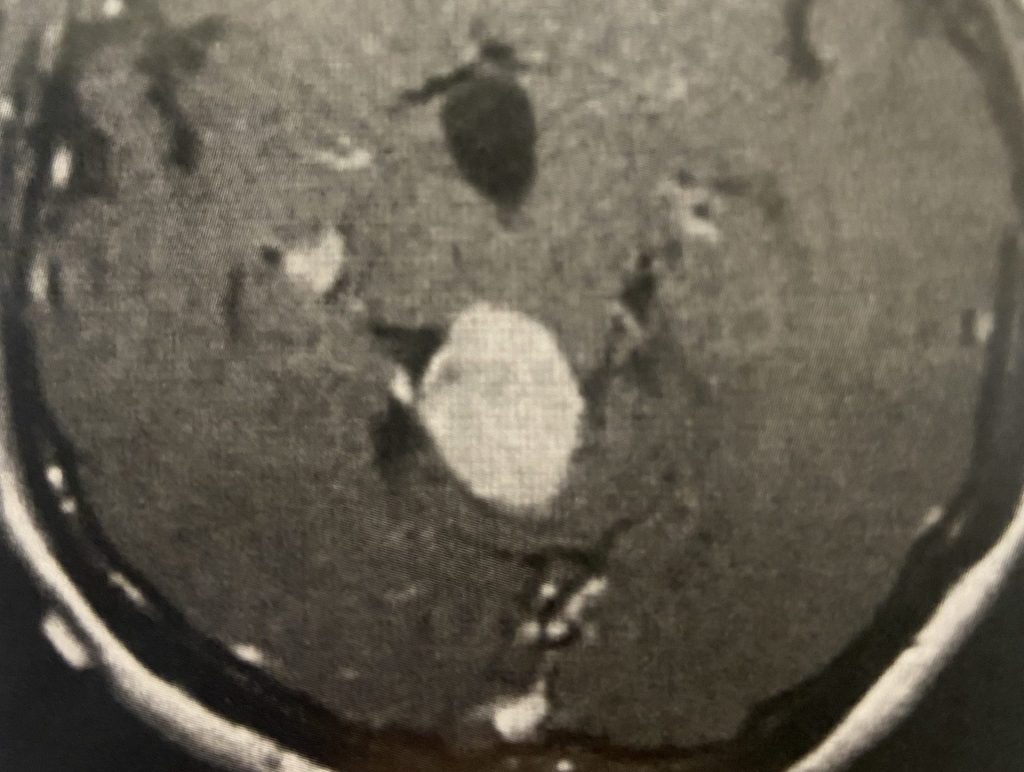

Brain:

Neurosurgeons Collaborate to Treat Giant Symptomatic Meningioma

Author: Ramin Rak M.D., F.A.A.N.S., F.C.N.S., Jonathan L. Brisman M.D., F.A.C.S., Read More!